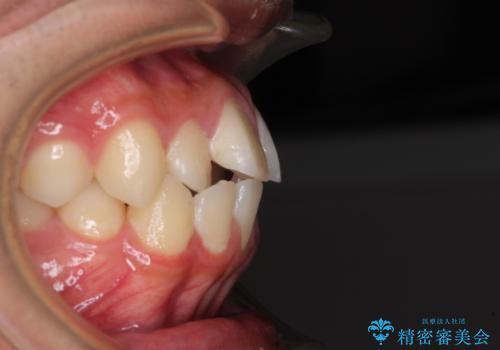

- 前歯のデコボコと口元の突出感を気にして来院された患者様です。

上下前歯がくちばしのように突出していたため、上下左右の第一小臼歯4本を抜歯し、ワイヤー装置にて矯正治療を行うこととしました。

左上は第二小臼歯が90度捻れており、状態が良くない歯であったため、左のみ第二小臼歯を抜歯することとしました。

上顎骨に対して下顎骨がやや前方位に位置しているため、下顎前歯をあまり内側に移動させることができず、口元の突出感改善は期待以上にはならないと予測しておりましたが、満足いくの引っ込み具合となりました。